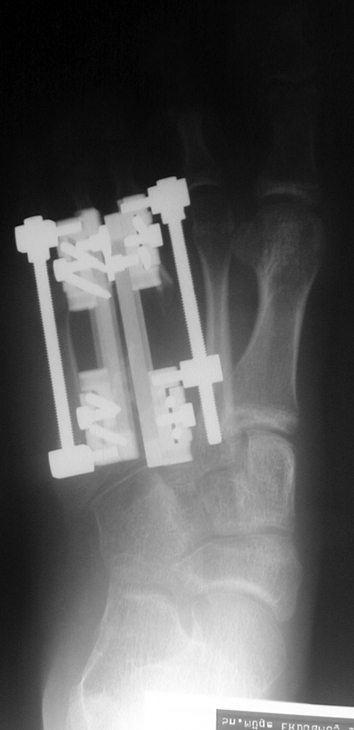

Doğuştan metakarp ve metatars kısalıklarının redavisi için pek çok teknik tanımlanmakla birlikte en çok akut uzatma sonrası kemik uçlarına greft konması ve distraksiyon osteogenezi (kallotasis) kullanılmaktadır. 1 cm.den daha fazla uzatma gereken olgularda kallotasis yöntemi önerilmektedir. Kliniğimizde de metatars ve metakarp uzatma için unilateral eksternal fiksatör ve sirküler eksternal fiksatör yardımıyla distraksiyon osteogenezi yöntemi tercih edilmektedir.